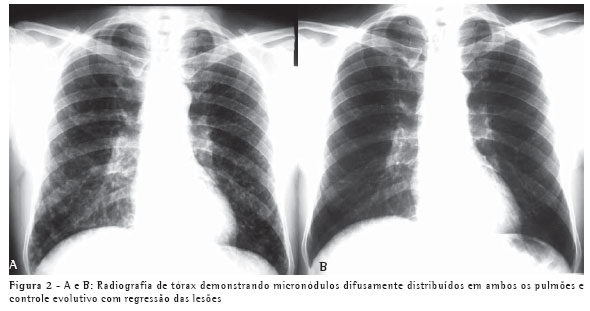

Um paciente, do sexo masculino, branco, de 50 anos, procedente de Blumenau, pedreiro, iniciou quadro semelhante e simultâneo ao do caso 1, dez dias após a limpeza da área referida com presença de fezes de morcego, ficando exposto a grande quantidade de poeira em ambiente fechado. Esteve hospitalizado por sete dias. O aspecto radiológico do tórax, apresentando micronódulos difusamente distribuídos em ambos os pulmões, e o controle evolutivo são demonstrados nas Figuras 2A e 2B.

conhecimento das síndromes clínicas e a suspeição clínica podem evitar o tratamento empírico. Os achados radiológicos, os exames negativos e a alta freqüência da tuberculose em nosso meio foram os fatores para o tratamento para tuberculose nos dois pacientes. O teste de imunodifusão, embora negativo nestes dois pacientes, tem alta sensibilidade, sendo positivo em aproximadamente 75% dos casos.(6) O tempo de exposição ao inóculo determina a gravidade da doença. Isto explica o fato de o segundo paciente, que varreu o local, ter apresentado uma forma mais grave da doença, com alteração radiológica pulmonar difusa e necessidade de hospitalização. Por outro lado, uma pequena exposição determina lesões pulmonares focais, como no caso 1.